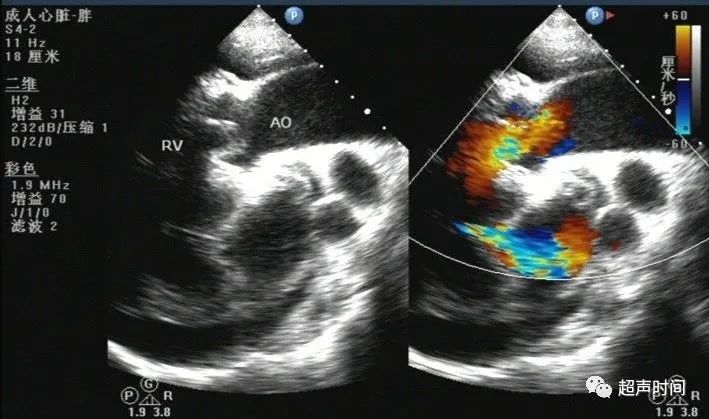

矫正型大动脉转位一例

容易被漏诊的矫正型大动脉转位